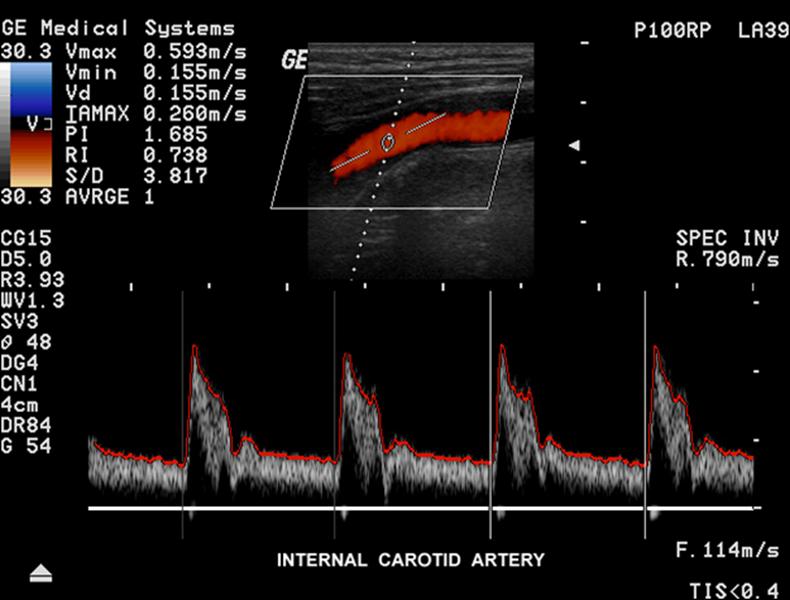

Explain the waveform of the CCA

Mimics both ICA and ECA waveforms

Where is the waveform?

CCA